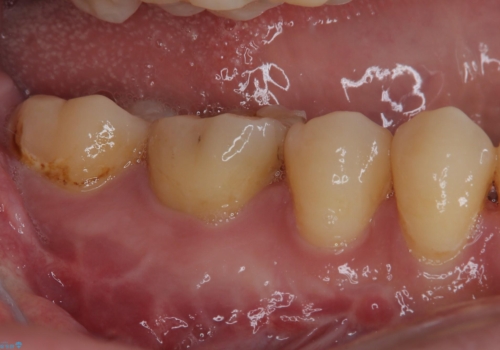

下顎大臼歯は根管治療がされている歯が咬合時に痛みを感じ、上顎の大臼歯2歯は冷たいものがしみる状態でした。

まずはしみる上顎の歯を仮歯に置き換え、その後下顎の根管治療を行った上で、異常が認められなければオールセラミッククラウンにて補綴治療を行うこととしました。

上顎は仮歯に置き換えた後に、それまでの痛みは一切感じなくなり、下顎も一度目の根管治療で痛みを感じることはなくなりました。